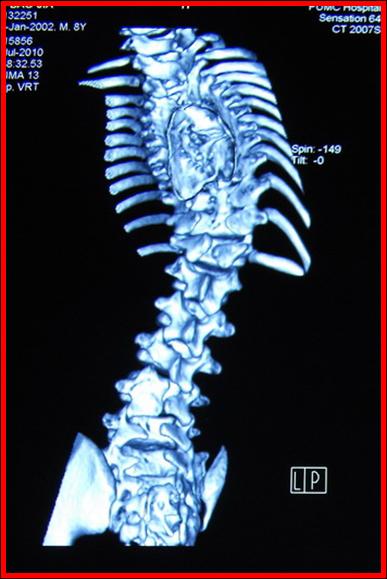

术前CT